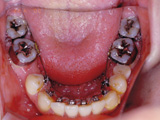

症例6:舌側矯正(見えない矯正治療)

治療前

治療途中

治療後